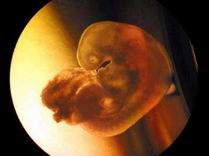

Human Embryo Nurtured Outside Mother's Body

A human embryo born in a fostering liquid is shown under a microscope to the public in Northeast China's Liaoning Province, April 15,2004. It's the first time in China that an embryo is successfully nurtured outside a mother's body.

Doctor Wang Tong of the province's Research Institute of Family Planning Science invented the new method, which can enable a mother diagnosed with certain illness to produce a baby with her egg outside her body and save her from risks. So far, Wang and his team have nurtured 28 such embryos.

(Newsphoto April 16, 2004)